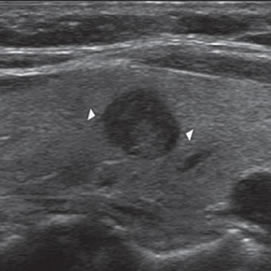

El patrón de calcificación periférica anular se consideró alguna vez que representaba un hallazgo benigno, pero un estudio demostró asociación con malignidad en 18,5% de los casos17. En ese estudio hubo una tendencia hacia un mayor riesgo de malignidad si el patrón periférico de calcificación era discontinuo (Figura 9) y un menor riesgo de malignidad si el patrón periférico de calcificación era liso y curvilíneo, en forma de cáscara de huevo (Figura 10).

Figura 9. Cáncer papilar, de forma redondeada, de 30 mm de diámetro,

hipoecogénico, con microcalcificaciones periféricas y discontinuas

(flechas). En el aspecto posterior las microcalcificaciones

forman un contorno lineal (flecha abierta).